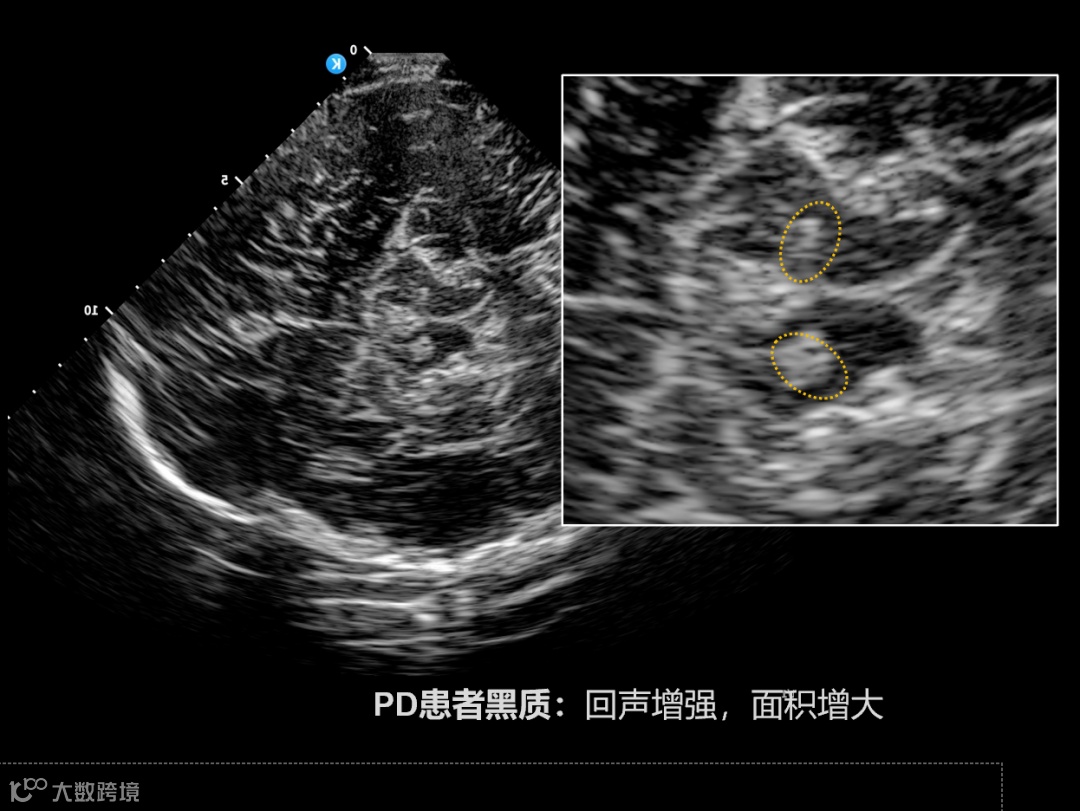

● 神经疾病研究

结合kOS平台探索抑郁症、阿尔茨海默病等脑部疾病的影像学基础。